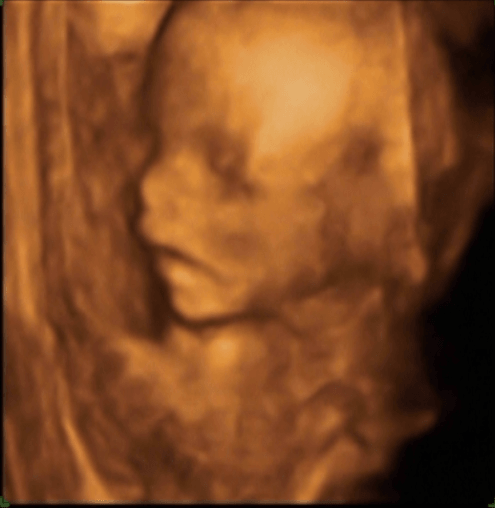

lekarz widząc moją minę na samą myśl o tym ( dużo się naslucham od dziewczyn, że to ohyda) powiedział " Spokojnie proszę mi zaufać " ciekawe czy sam próbował